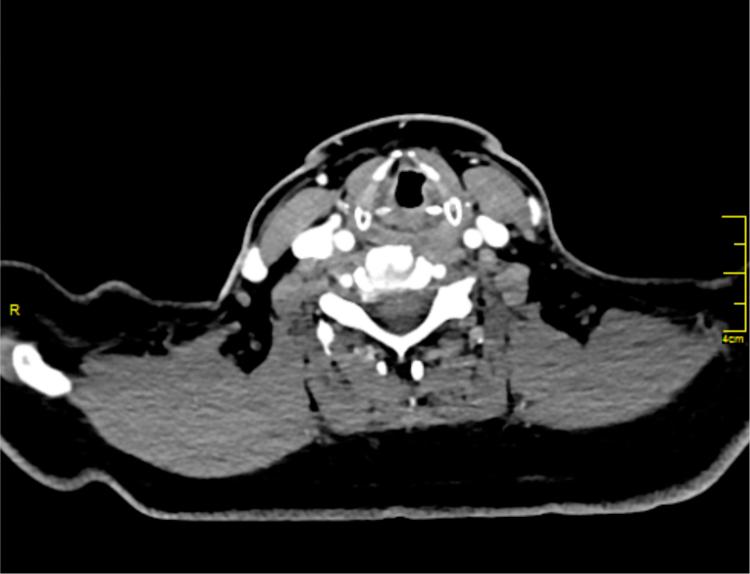

Hoarseness: an unusual presentation of primary thyroid lymphoma with laryngeal infiltration.

Braz J Otorhinolaryngol. 2016 Nov-Dec;82(6):737-740. doi: 10.1016/j.bjorl.2015.05.006. Epub 2015 Sep 7.